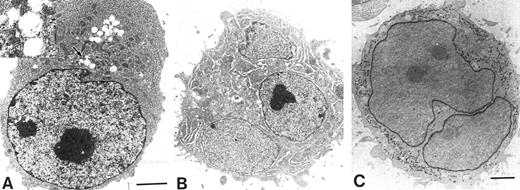

Electron microscopic photographs of UT-7/GM cells cultured under various conditions. UT-7/GM cells were cultured with EPO (10 U/mL) or TPO (100 ng/mL). One month later, the cells were obtained for the analysis. (A) A representative UT-7/GM cell cultured with EPO. The cytoplasm of the cell is darker than the nucleus, implying the presence of hemoglobin. Insert shows higher magnification of atypical theta granules (arrow). Counterstaining was performed with lead citrate and uranyl acetate. Scale marker indicates 2 μm. (B) A representative UT-7/GM cell cultured with TPO. A multinucleated cell having developed demarcation membrane systems is shown. (C) Detection of PPO activity in a cell cultured with TPO. PPO activity is observed in nuclear envelope and rough endoplasmic reticulum of a large binuclear cell. Scale marker indicates 2 μm.

EPO induces erythroid differentiation of UT-7/GM cells.When the UT-7/GM cells were cultured with EPO instead of GM-CSF, we noted that the cell pellet had turned reddish. This observation suggested that the UT-7/GM cells had differentiated into erythroid cells having a high concentration of hemoglobin in the presence of EPO. To confirm this possibility, we stained the cells with dianisidine to detect hemoglobin synthesis. As shown in Fig 3D, when the cells were treated with EPO for 2 weeks, the majority of the cells were positive for dianisidine staining. Dianisidine-positive cells increased from zero to more than 90% within 2 weeks. The cytospin smear contained cells having pale spots in the perinuclear areas and some cells became condensed. Electron microscopic analysis revealed that, in addition to developed Golgi apparatus, a theta granule16 was detected (Fig 4A). The cytoplasm of the cell was darker than the nucleus, implying the presence of hemoglobin (Fig 4A). To further characterize the EPO-treated UT-7/GM cells, we examined the expression of EPOR and γ-globin mRNAs by Northern blot analysis. The level of EPOR and γ-globin mRNAs clearly increased after the treatment with EPO for 4 weeks (Fig 5). These observations confirmed the hypothesis that UT-7/GM cells became mature erythroid-like cells in the presence of EPO.

TPO induces megakaryocytic differentiation of UT-7/GM cells.When the UT-7/GM cells were cultured with TPO alone, some cells became bigger than before. As expected, the cytospin smear of TPO-treated UT-7/GM cells contained cells similar to mature megakaryocytes with multilobular nuclei (Fig 3B). The electron microscopic analysis revealed that large cells have a developed demarcation membrane in the cytoplasm and that most of the cells had positive platelet peroxidase activity (Fig 4B and 4C). This finding suggested that some of them differentiated into more mature megakaryocytic cells in the presence of TPO. To investigate whether TPO indeed induced megakaryocytic differentiation of UT-7/GM cells, we checked the expression of GPIIb and PF-4 mRNAs by Northern blot analysis. As shown in Fig 5, PF-4 mRNA was clearly detected in 4 weeks, and the intensity of GPIIb mRNA band definitely increased. Moreover, the time course study demonstrated that PF-4 mRNA was slightly detected in 2 weeks and clearly detected in 3 weeks (Fig 7B). These observations suggested that TPO induced megakaryocytic differentiation of UT-7/GM cells.